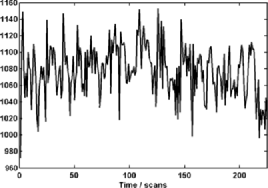

The subject in Figure 3 seems to exhibit strong deviations from stationarity—in fact, the -value associated with this subject is below based on the bootstrap test given in Section 7. It should be stressed that the change detection is a global hypothesis test combined over all components considered. In this way, while taking more components will help increase the chance that the change is present in one, it will come at the cost of the size of the change needed in finite samples for an omnibus test of this type. However, the subject shown in the figure did cause a rejection of the null hypothesis of no change both in the 64 and 125 subspace size omnibus tests. While the pictures in Figure 3 indicate that an epidemic change is indeed a good first approximation for the nonstationarities occurring for this particular subject, more deviation (maybe more change-points) does seem to be present. In Figure 4, a second subject is shown with a much smaller deviation from stationarity (most of the components seem to have little to no possible mean change present), which is significant but does not survive the false discovery rate (FDR) correction (see Section 4.3).

Figures 5–7 show three component time series selected for their different properties. The component in Figure 5 can be seen to be a candidate series for a change to have occurred with the resulting change corrected series visually appearing much more stationary (although it is likely there are other nonstationarities present as well). This series, from subject 01018 in the connectome data set, was found to have evidence of nonstationarities when the sample version of the statistic (given in Section 6.2) was tested on both a 64 and 125 component projection.

When testing subject 48501 from the connectome data, from whom the components can be seen in Figure 4, an epidemic change seems to be quite a good model for several components, but only a small part of the time series deviates from stationarity. For example, component 7 in Figure 6 shows a less pronounced but still plausible epidemic change compared with component 23 of subject 01018 in Figure 5. However, as can be seen in another component (Figure 7) from subject 48501, some of the components seem to be stationary without any change present.

Finally, in Figure 2 the subject shown has components which do not indicate level shifts and, in fact, the null hypothesis is not rejected for this subject, either with or without FDR correction.